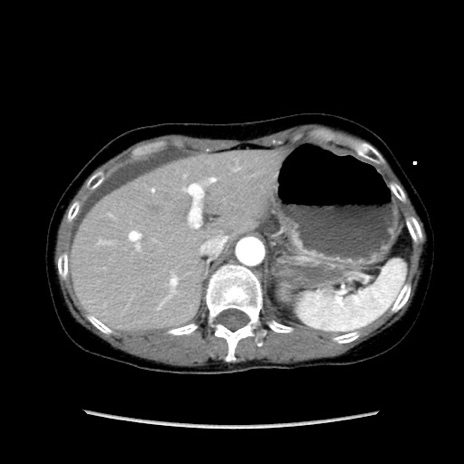

症例32(横断像)

【症例】40歳代 女性

【主訴】上腹部痛、嘔気・嘔吐

【現病歴】約9時間前頃から急に上腹部痛、嘔気、嘔吐が出現。改善しないため救急要請。

【既往歴】子宮頚癌(広汎子宮全摘術、放射線療法)、腸閉塞

【身体所見】腹部:平坦、軟、腸雑音亢進、上腹部を中心に腹部全体に圧痛あり。

【データ】WBC 8400、CRP 0.03